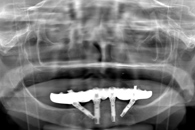

下顎のインプラント治療を行って、再び噛める喜びをとりもどしたAさんのケースです。

<Aさんのケース>

①総入れ歯を固定するためのインプラントを埋め込んだところです。